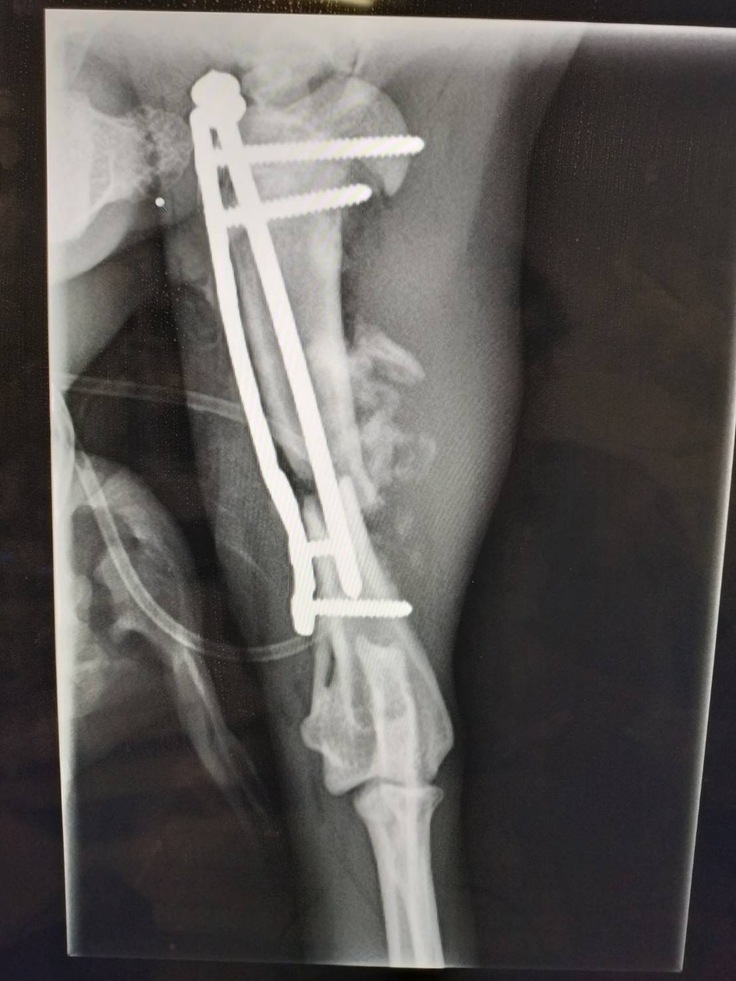

手術で修復したことがわかるレントゲン

ちょっと手の先に麻痺が残りました